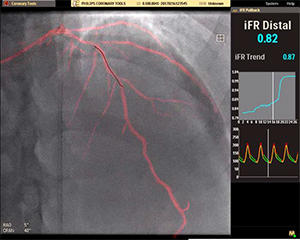

(株)フィリップス エレクトロニクス ジャパンは,6月30日より,X線血管造影撮影装置Azurion(アズリオン),Allura(アルーラ)ファミリーに対応する経皮的冠動脈形成術(PCI)を支援する最新*1システムソリューション 「iFR Roadmap(アイエフアール ロードマップ)」の販売を開始する*2。

iFR*3の値とプルバックカーブをリアルタイムで自動表示し ,心臓冠動脈疾患の低侵襲性治療を積極的に支援する。

2. 血管画像とiFR値の比較レビュー

同一画面で比較レビューができるため,計測後の治療戦略が立てやすくなる。

*3 iFR(instantaneous Flow Reserve)とは,フィリップス独自の機能的な虚血評価指標。最大充血を惹起する血管拡張剤を使用する必要がなく,冠動脈の狭窄や病変を評価することができる。